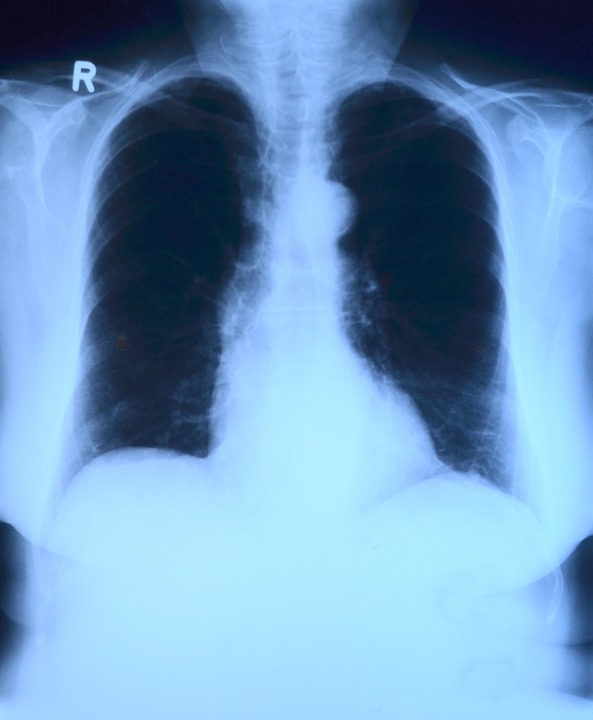

Адміністрація СІЗО повідомила суд про погіршення здоров`я Заявника та неможливість здійснення лікування в СІЗО з огляду на відсутність для цього відповідних умов. Через деякий час справу було повернуто на дорозслідування, а Заявника – звільнено з-під варти. Після звільнення з-під варти Заявник неодноразово проходив лікування, внаслідок якого було виявлене погіршення стану його легенів.

8. 13 січня 2011 року Генічеська центральна районна лікарня видала довідку, що з 2009 року заявник страждав на туберкульоз. У нього була активна форма захворювання, яка була небезпечною для інших, а тому вимагала лікування.

14. Упродовж тримання під вартою здоров’я заявника проводжувало погіршуватися. Його перевозили до різних лікарняних закладів для проходження обстежень, зокрема 15, 18, 20 і 21 жовтня та 01 грудня 2011 року. Під час одного з таких обстежень

18 жовтня 2011 року заявнику діагностували пухлину підшлункової залози. Йому було рекомендовано пройти спеціальне стаціонарне лікування туберкульозу. Як стверджувалося, тоді він не отримав жодного лікування у зв’язку з його захворюваннями.

2012 року. У медичній довідці без дати (але, як стверджувалося, виданій 07 травня 2012 року) заявнику було діагностовано ВІЛ, IV стадія. Згідно з медичною довідкою від 14 травня 2012 року було виявлено погіршення стану легенів заявника.

18. Згідно з медичною довідкою від 21 вересня 2012 року лікування заявника ускладнювалося у зв’язку з появою резистентності до протитуберкульозних лікарських препаратів.